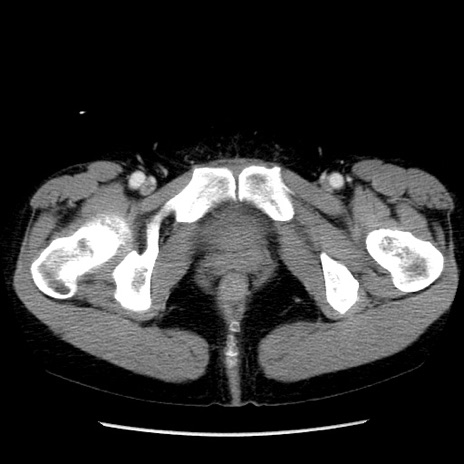

症例6(横断像)

【症例】50歳代女性

【主訴】下腹部痛

【現病歴】本日朝より下痢2回あり。 昼食を食べた後、嘔吐3回、下腹部痛認め、症状軽快せず、当院救急搬送。

【既往歴】卵巣癌術後(8年前に当院で卵巣摘出)

【身体所見】 意識清明、腹部:平坦、腸蠕動音→、やや硬、下腹部自発痛・圧痛あり、反跳痛あり、筋性防御なし。

【データ】WBC 16000、CRP 0.01